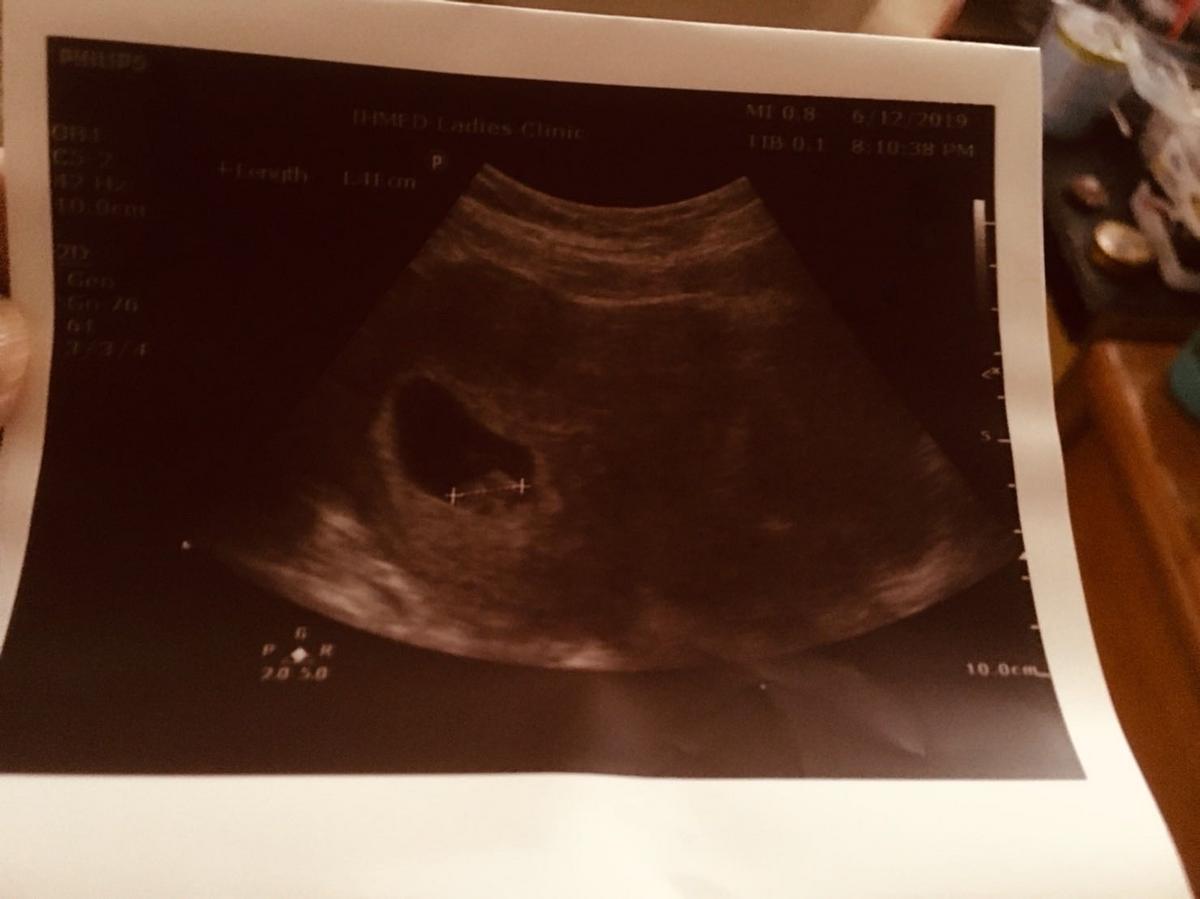

今天是2019年的6月4日早上媽媽去診所檢查照超英波時,這一天媽媽聽到妳的心跳聲了,醫生跟佩宜姨姨都說妳的心臟好有力喔!媽媽就對醫生說我們每天都有未妳的心臟成長禱告,因為當時的週數是長心臟的時候。醫生接著說很好,繼續禱告!

在6月26日給醫生照超音波時有看到妳的手手跟腳腳,而且醫生說妳很活潑的動來動去。說實話媽媽實在是看不出來手腳,但醫生的火眼金睛真的神準啊!